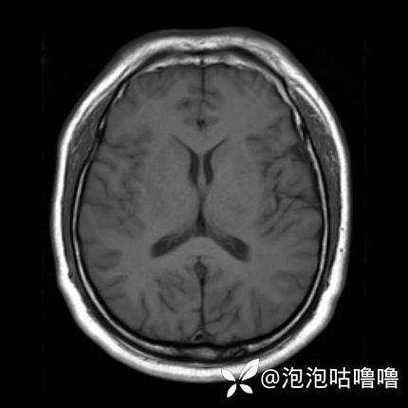

头颅MRI(磁共振成像):

- DWI序列(弥散加权成像): 这是目前最早、最敏感发现急性脑梗的检查,在发病后30分钟到1小时内,梗塞灶就会在DWI上显示为明显的高信号(白色),可以说,MRI是诊断早期脑梗的“金标准”。

- 缺点: 检查时间长、费用高、部分患者体内有金属植入物无法检查。